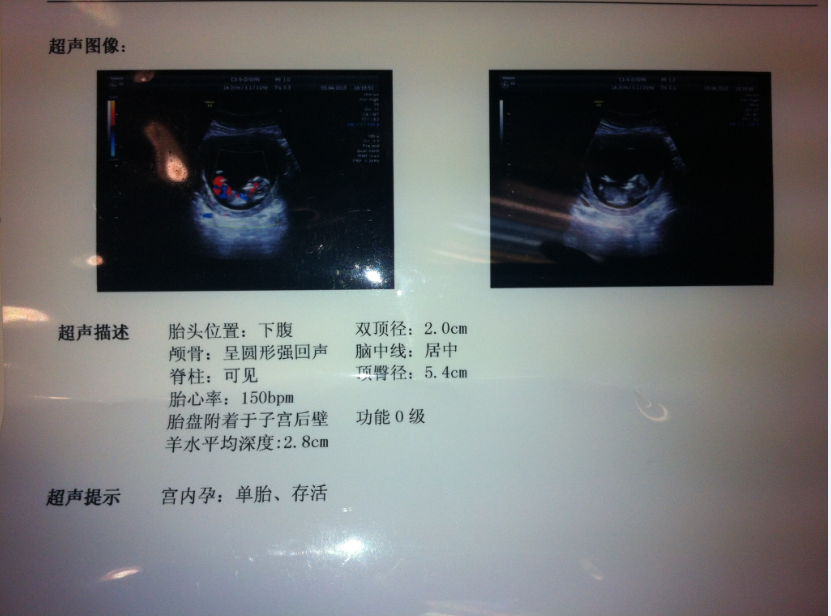

我媳妇怀孕三个月了,昨天去医院检查,胎儿各项发育正常,想问B超上的红色和蓝色是什么意思?

那个红色和蓝色是机器扫描出来为了成像的,没有什么临床意义 的,亲不需要纠结这些,你还是多多注意下怨然你老婆哦~! 怀孕第三个月虽然是关键期,但由于胎儿体积尚小,所需的营养不是注重量的多少,而是注重质的好环,尤其需要蛋白质、糖和维生素较多的食物,受孕11周以后,由于胎儿迅速成长和发育,需要营养也日渐增多。 从这个时期起,不仅食品的质要求高,而且量也逐渐要多。充足而合理的营养是保证胎儿健康成长的重要因素,也是积极开展胎教的基本条件。 由于早孕反应,以及增大的子官压迫胃和其他消化器官,孕妇常会出现消化不良,食欲不振等情况。这时孕妇除了少吃多餐外,在饮食结构方立报某面应挑选容易消化的、新鲜的食物,尽量避免吃油炸沃叹、辛辣的食物。